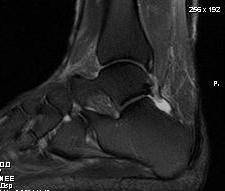

MRI

Retrocalcaneal bursitis with Haglund's

Partial tearing at insertion with retrocalcaneal bursa

Tendon thickening, Haglund's deformity and retrocalcaneal bursa

MRI grading

- Grade I: 6 - 8 mm thickening

- Grade II: > 8 mm tendon thickness with < 50% tendon degeneration

- Grade III: > 8 mm tendon thickness with > 50% tendon degeneration